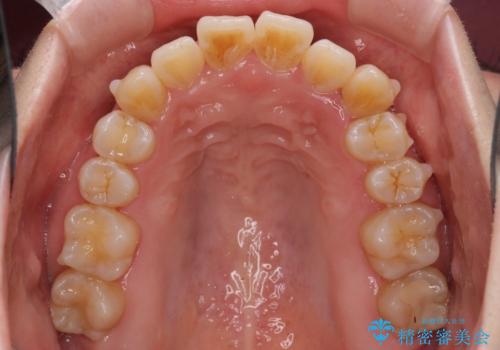

インビザラインでの歯列全体の後方移動は時間がかかりますが、しっかりと装着時間を守っていただいたので、スッキリとした口元に仕上げることができました。